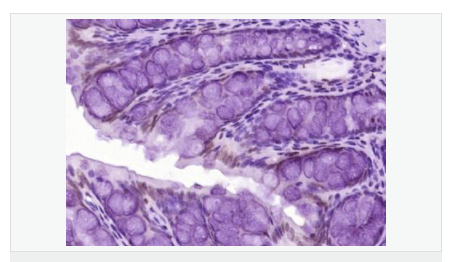

| 產品應用 | WB=1:500-2000 ELISA=1:5000-10000 IHC-P=1:100-500 IHC-F=1:100-500 ICC=1:100-500 IF=1:100-500 (石蠟切片需做抗原修復) not yet tested in other applications. optimal dilutions/concentrations should be determined by the end user. |

| 細胞定位 | 細胞核 細胞漿 |